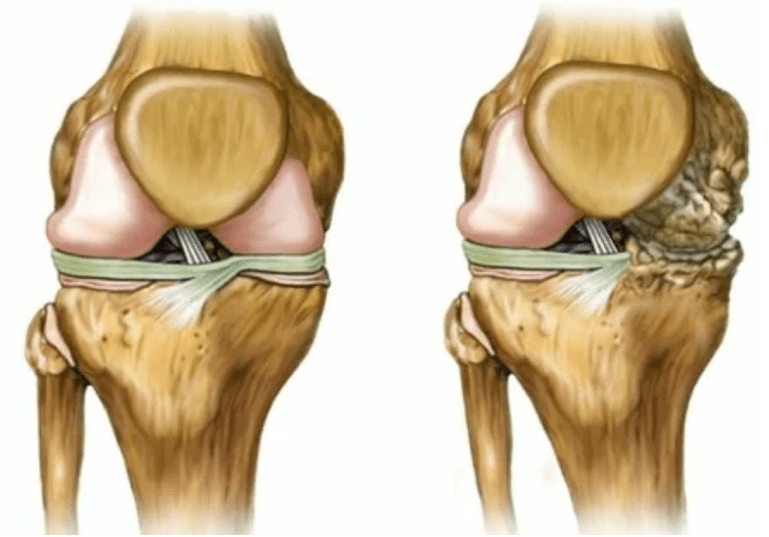

- 1 grāds. Morfoloģiskie traucējumi jau ir sākušies, bet tie vēl nav pamanāmi. Patoloģija galvenokārt ietekmē sinoviālā šķidruma stāvokli, kas sliktāk piegādā skrimšļa audus ar barības vielu sastāvdaļām, samazinot skrimšļa izturību. Lieka uz locītavām izraisa iekaisumu un sāpes.

- 2. posms. Piegādes deficīta dēļ tiek iznīcinātas nepieciešamās kasetnes, uz skrimšļa virsmas veidojas kaulu izaugumi. Sāpes iegūst izteiktāku raksturu, pastiprinoties pēc ilgas atpūtas, tiek izvadīts mazs fiziskais darbs. Sāpes pavada iekaisums. Muskuļi ir izstiepti, kas noved pie vājiem vai vidēji traucētām motoriskām funkcijām.

- 3 grādi. Bieži vien ir sāpes, locītavas izmaiņu dēļ ir grūti pārvietot ekstremitāti. Bojājumi ir plaši, kļūst pamanāmi kailajam izskatam. Apvienotās vietas deformācija notiek, skartā zona uzbriest un kļūst sarkana. Ekstremitāšu ass ir traucēta, kas noved pie kustības sarežģītības. Patoloģiskās izmaiņas provocē saites saīsināšanu. Parādās apakšgrupas un kontraktūras. Blakus esošie muskuļi ir saīsināti vai izstiepti, no kura tiek novājināta kontraktilās funkcijas.